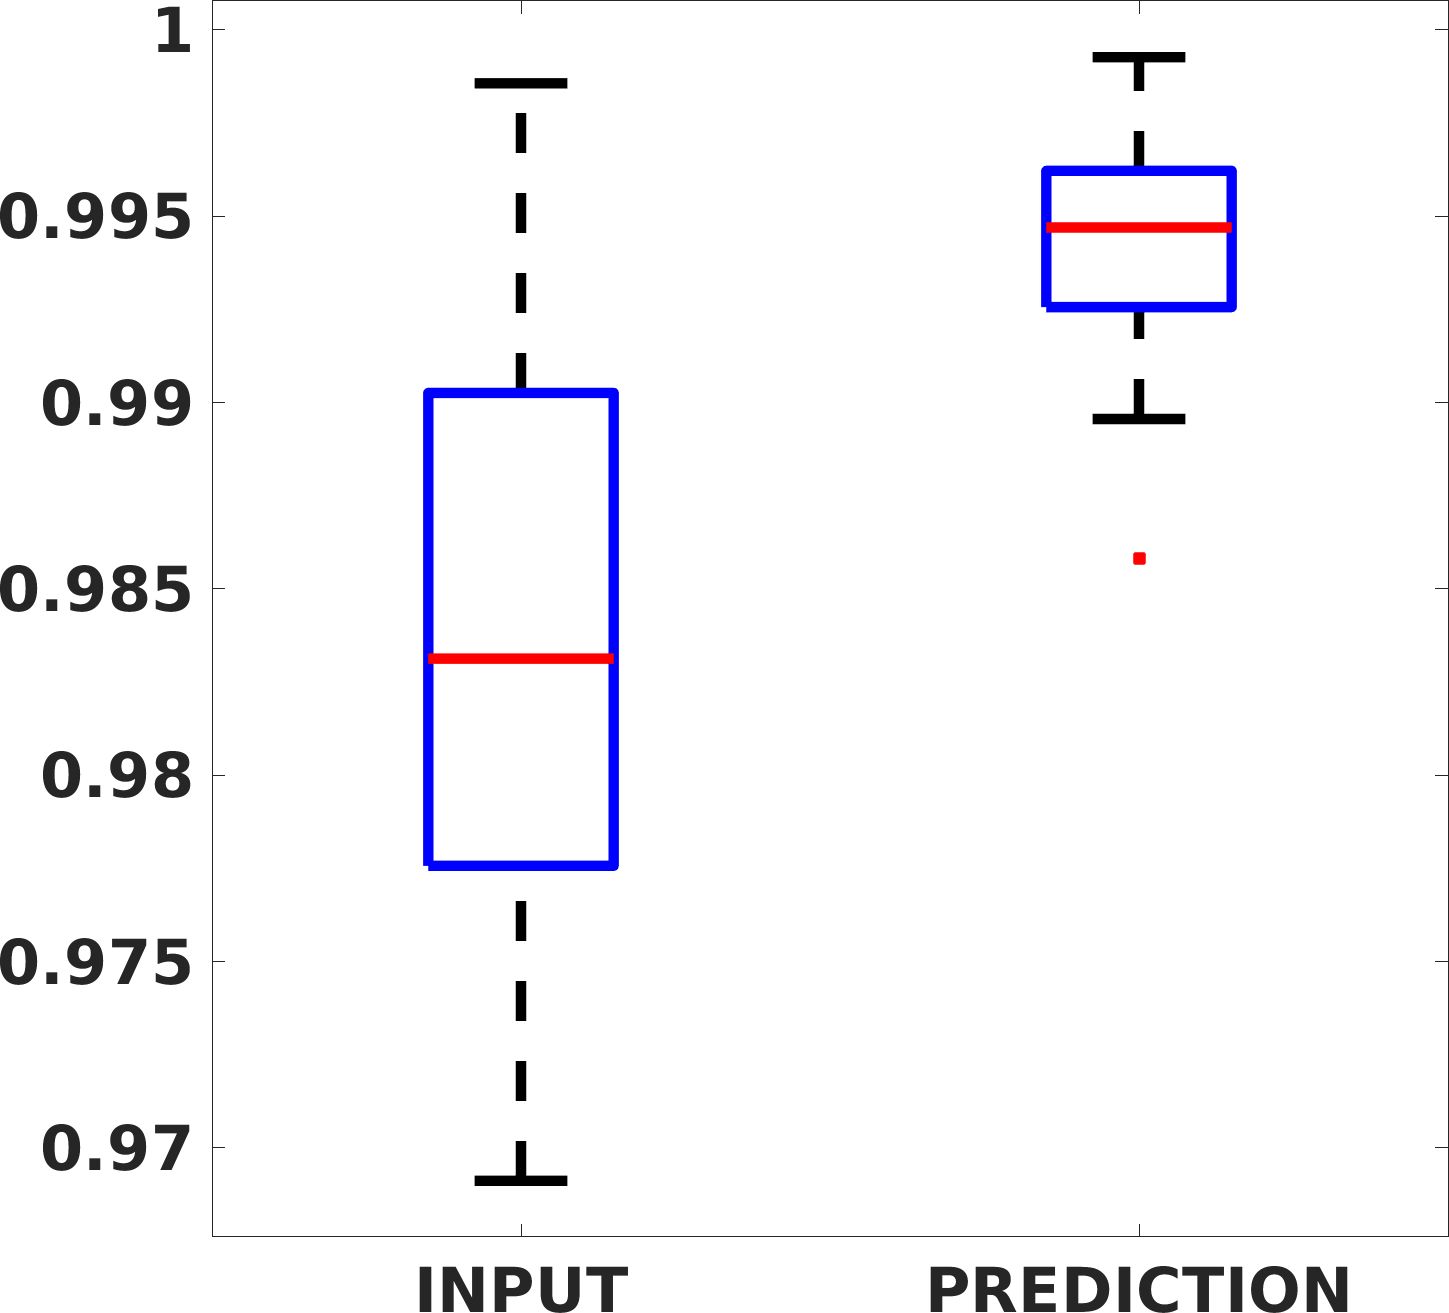

Fig. 7(a-b-c, left) shows the box plot of the statistics of the PSNR on three different anatomical districts, comparing the target images with the prediction and the cubic convolution, respectively. The metrics are computed on a data set of 200 images of the same district and with the same up-sampling factor. We report that the PSNR median value improves of on obstetric 2X raw images, on cardiac 2X raw images, and on abdominal raw 4X images.

Fig. 7(a-b-c, right) shows the histogram of the absolute value of the error with respect to the target image, of the prediction and Cubic convolution results, respectively. The histograms show the number of pixels where the prediction error is lower than 5 (i.e., the first bin of the histogram), which means very similar to the target when visually analysing the images. From the Cubic convolution to the predicted images, this value increases of on obstetric 4X raw images, on cardiac 4X raw images, and on abdominal 4X raw images.

Fig. 8 shows the box plot of the SSIM (a-b-c, left) and MAE (a-b-c, right) quantitative metrics, as performed for PSNR metric. Also, these metrics show that our method improves the results of Cubic convolution both in terms of average value and variability. For example, the SSIM median value improves of on obstetric 4X images and the MAE median value improves of on cardiac 2X images.